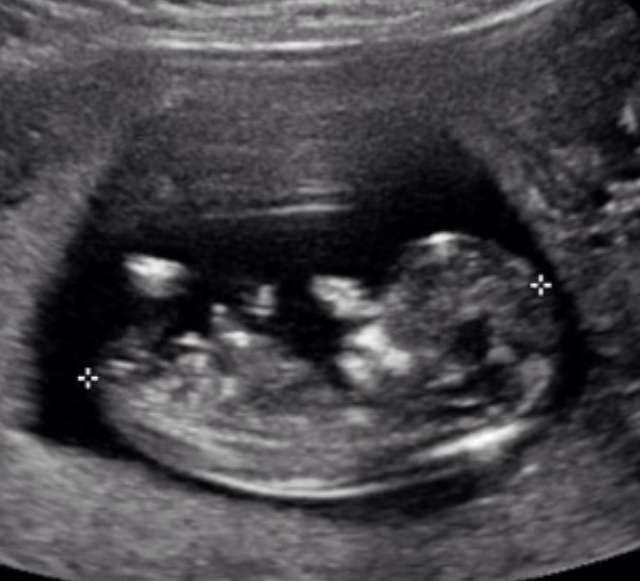

Hi everyone was wondering if you wouldn't mind taking a guess for me?

Hm. Tentative girl lean.

Thanks for your guess Abifasc. Is the nub the long line with the fork at the end?? Or the two white lines in the middle?

What week was this taken?

Hi there this shot was taken at 12 weeks 5 days

Any other guesses thanks

The two white lines mean I'm leaning slightly pink

Thanks Tishtastosh I thought those two white lines might be a cord but stumped at this theroy I can't tell what I'm looking at lol